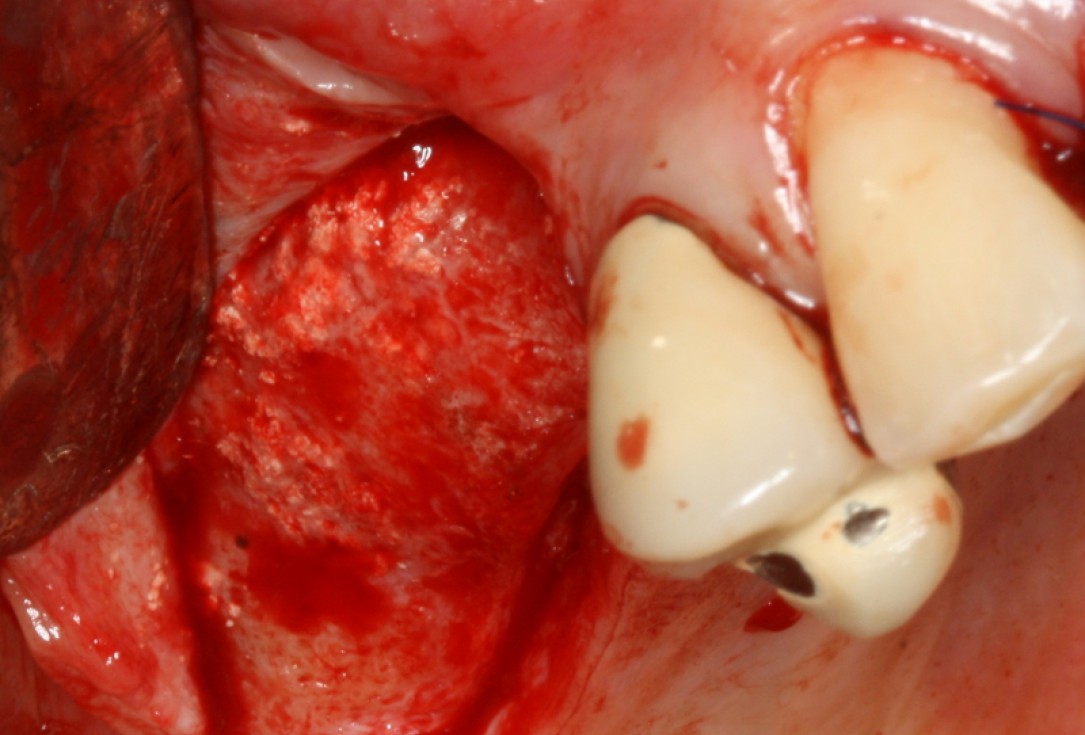

Surgical presentation of the alveolar ridge with reduced amount of horizontal bone available